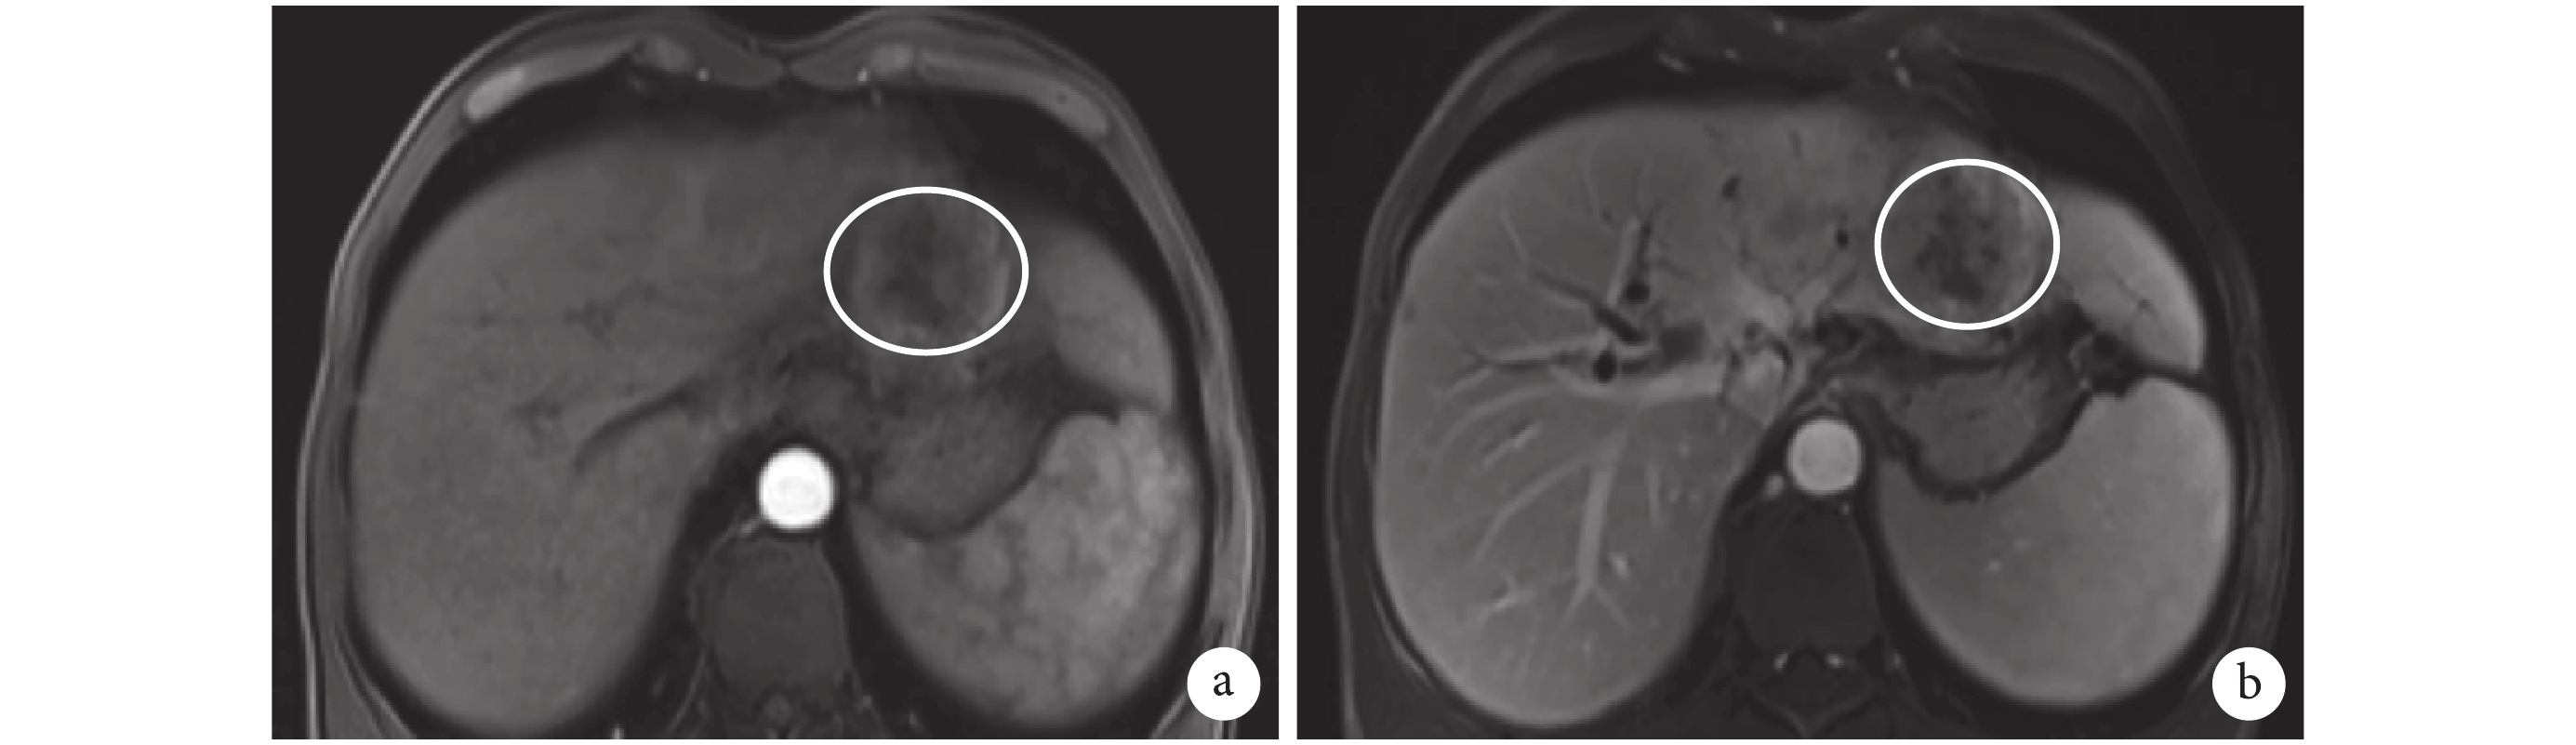

四川省腫瘤醫院影像科任靜主任醫師認為:患者的 MRI 圖像提示肝門區見一 3.7 cm×2.4 cm 大的實性占位,并向右肝管和左肝管內延伸;腫瘤向左肝管內延伸至左外葉膽管,向右延伸至膽管右前支和右后支匯合處,向下延伸至膽總管中段(圖 2);門靜脈左右支、肝動脈左右支及其主干均未見腫瘤侵犯(圖 3),肝門未見腫大淋巴結;脾臟明顯增大。MRI 掃描的 1~3 個層面中見左肝外葉有一 4.5 cm×4.5 cm 大的實性結節,動脈期明顯強化、門靜脈期強化減弱(圖 4),影像學考慮 HCC,因此之前的影像學閱片診斷錯誤。